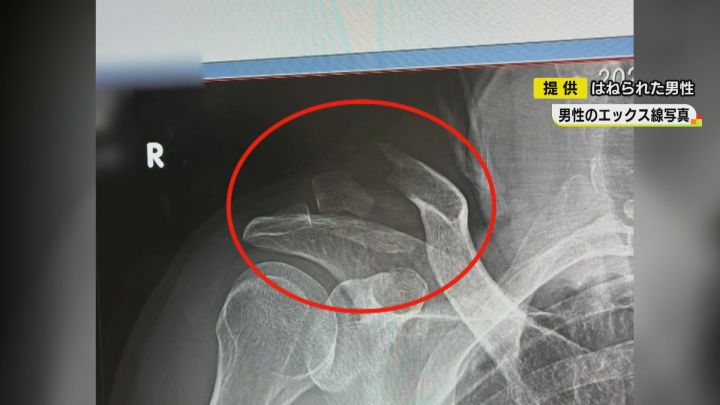

X線写真を見せてもらうと、右の鎖骨が折れているのが分かります。さらに、ろっ骨も折るなど重傷を負いました。